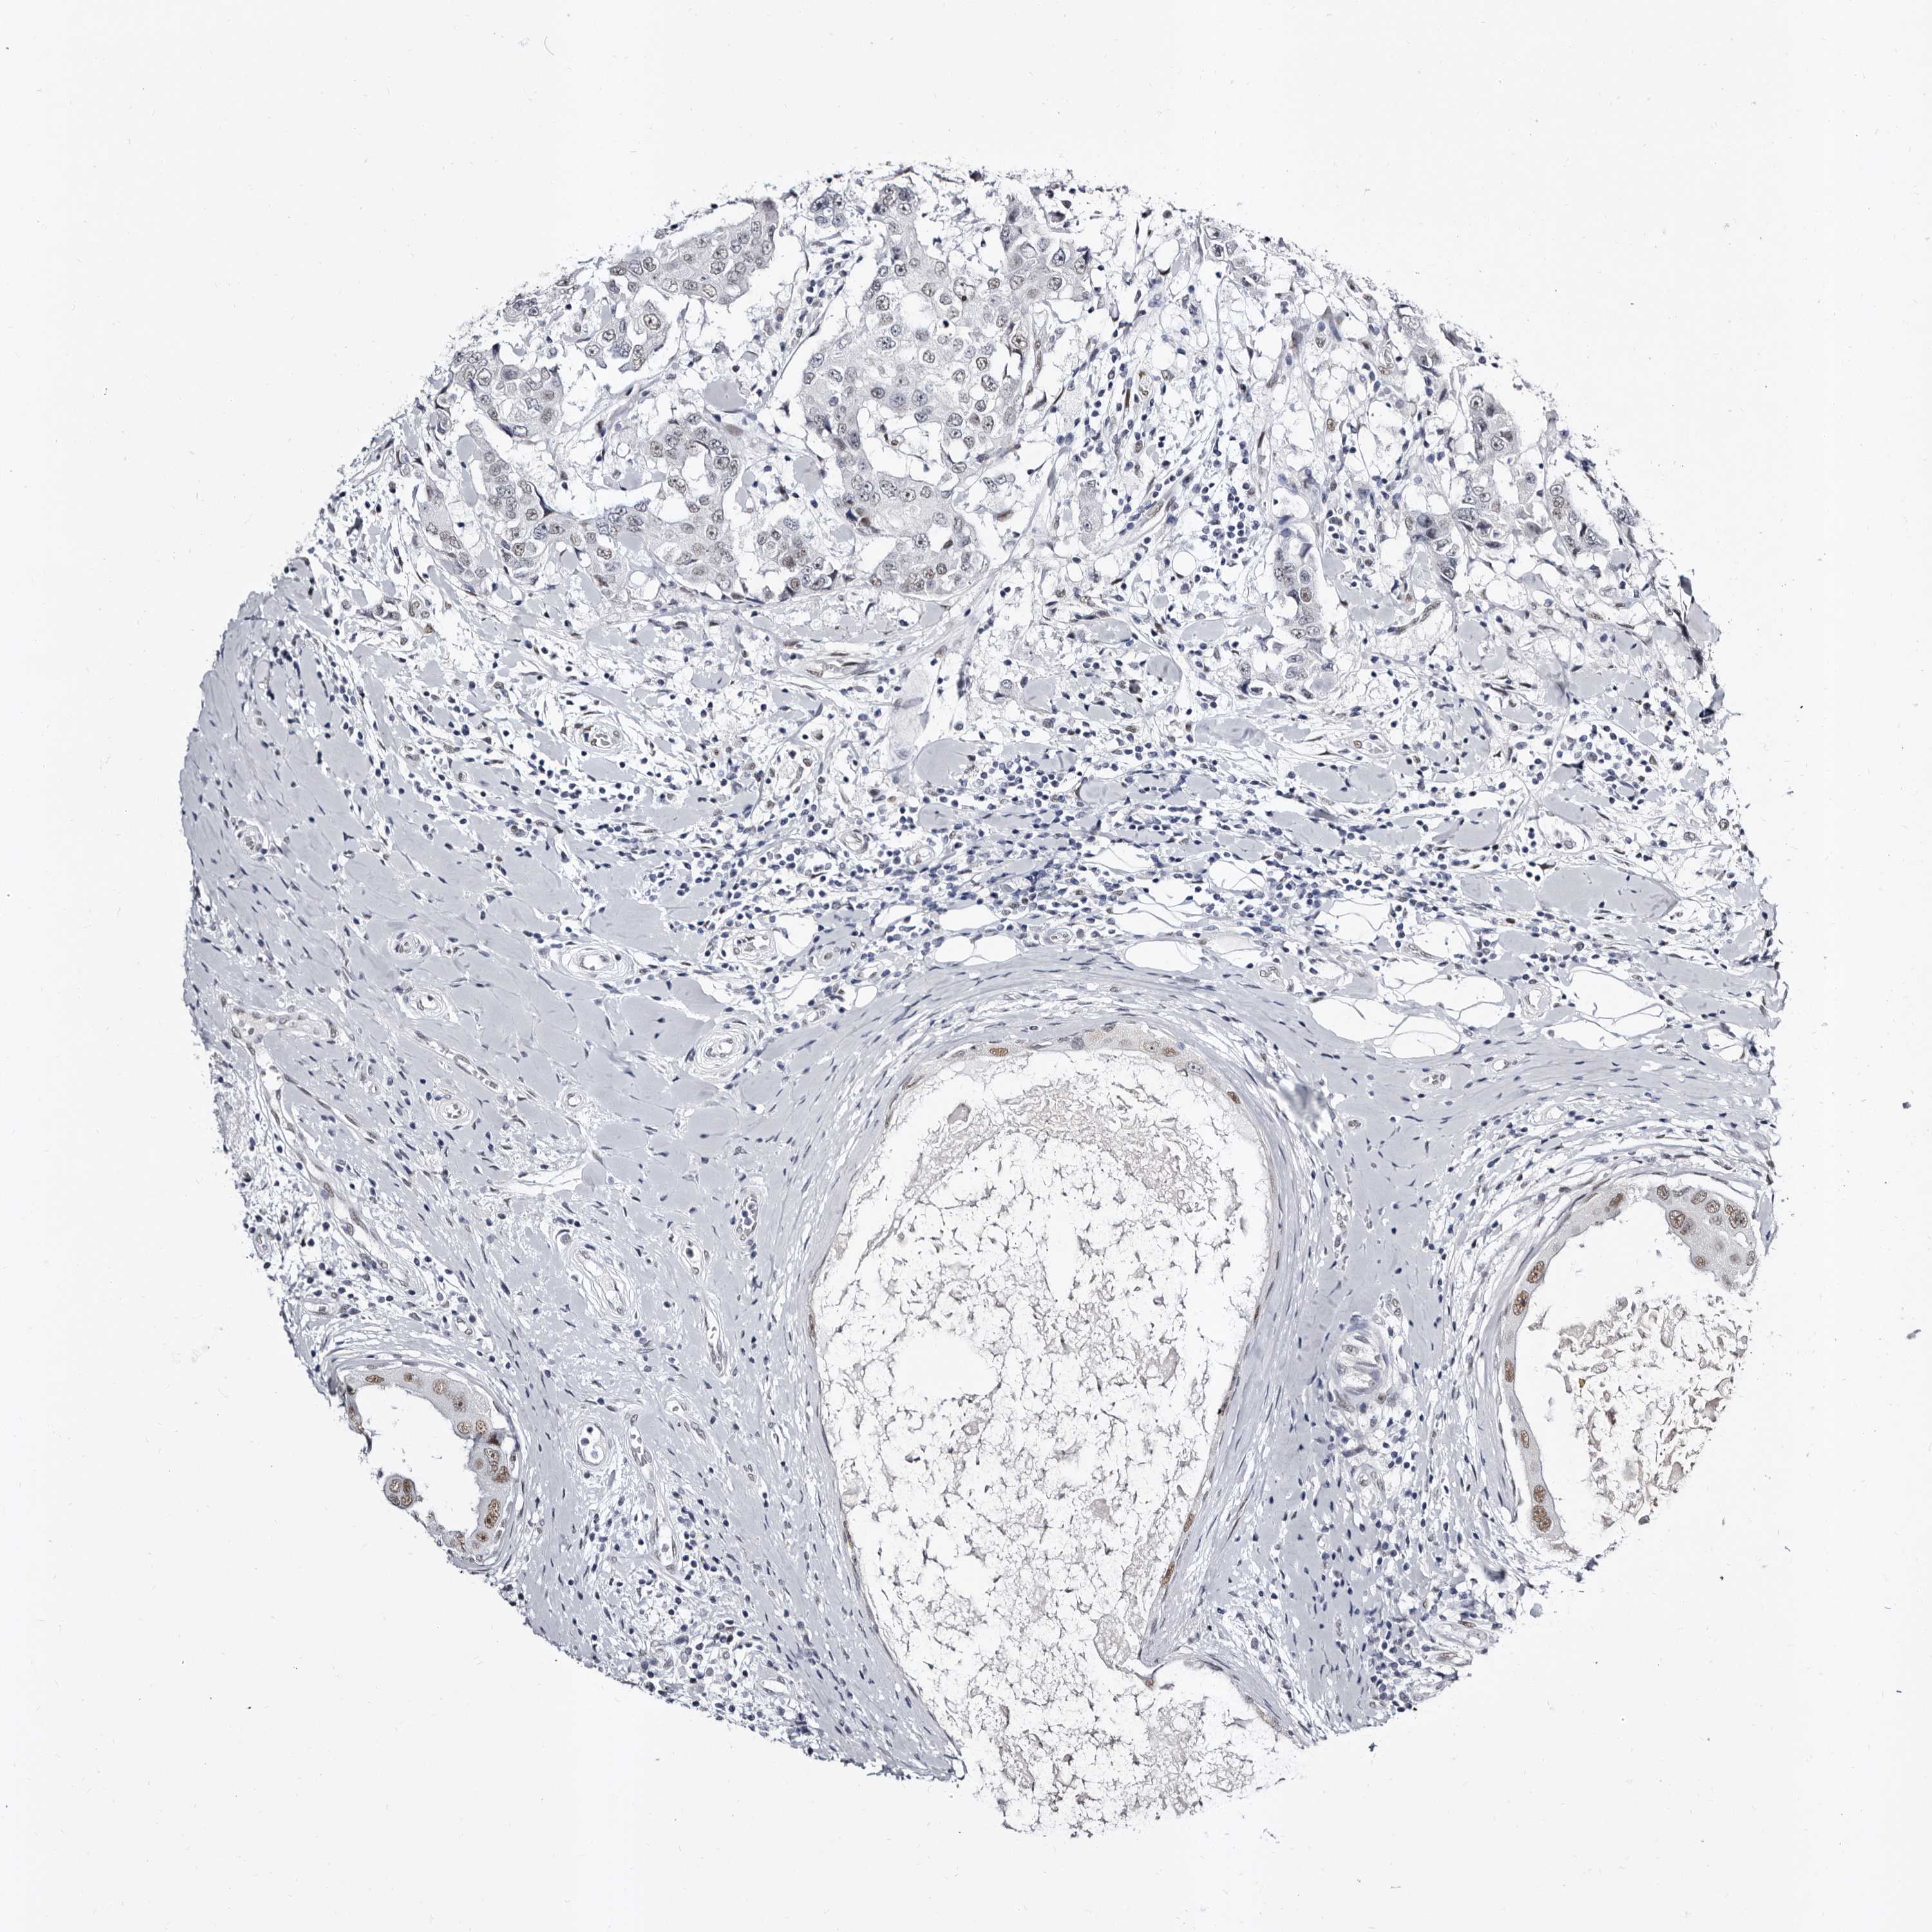

BRCA TCGA BRCA VALIDATION PROTEIN EXPRESSION